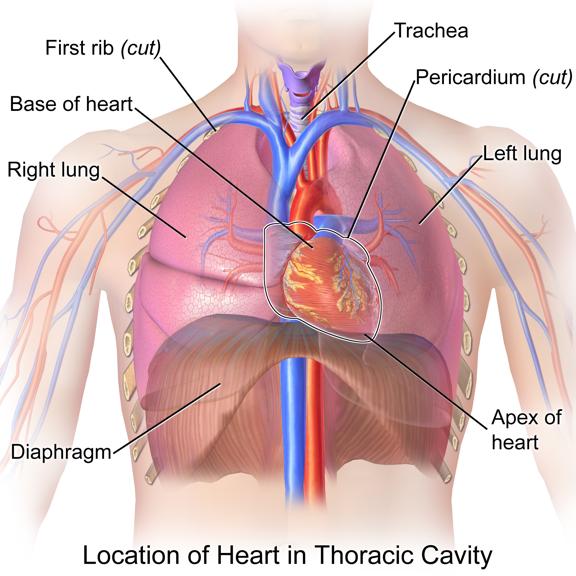

کلیهها، اندامهایی لوبیایی شکلاند و به تعداد دو عدد در طرفین ستون مهرهها و پشت محوطۀ شکمی قرار دارند. اندازۀ کلیه در فرد بالغ، تقریباً به اندازۀ مشت بستۀ اوست. به علت موقعیت قرارگیری و شکل کبد، کلیۀ راست قدری پایینتر از کلیه چپ واقع است.

در سطح جلویی کلیه راست بخشی از کبد و کولون بالارو و در سطح جلویی کلیه چپ بخشی از لوزالمعده و کولون پایینرو قرار دارد.

هر دو کلیه در سطح زیرین دیافراگم قرار دارند.

سطح پایین هر دو کلیه توسط دندهها محافظت نمیشود.

دندههایی که از کلیه محافظت میکنند به استخوان جناغ اتصال ندارد، اما به ستون مهره مفصل شدهاند.

دندهها ازبخشی از کلیه محافظت میکنند. علاوه بر این، پردهای از جنس بافت پیوندی به نام کپسول کلیه، هر کلیه را در بر گرفته است.

ششها را نیز پردهای دو لایه از جنس بافت پیوندی در بر گرفته است.